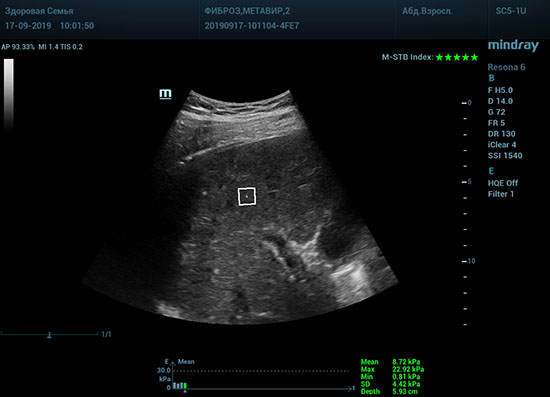

Определение плотности печени. Не ошибся ли оператор при измерении эластических свойств печени? Для оценки критериев качества предусмотрен индекс MBT, который покажет насколько «твердой» была рука оператора и двигалась ли печень. При MBT 5* рука тверда и показатели достоверны. Для оценки качества результатов используется IQR индекс, отображающий колебания показателей в точке измерения при расчете медианы. Показатели при IQR <30% считаются приемлемыми. Техника сканирования через межреберные промежутки требует размещение окна интереса на несколько сантиметром ниже капсулы, для исключения эффекта реверберации. Установка ROI на паренхиму без захвата сосудов, для исключения погрешностей измерения.

Стадия фиброза определяется по системе METAVIR Staging, построенной на данных биопсии и сопоставлении с данными эластографии. Своевременная диагностика фиброза, и начало его лечения, залог благоприятного исхода заболевания.

• METAVIRF2 – Портальный фиброз с вовлечением нескольких перегородок